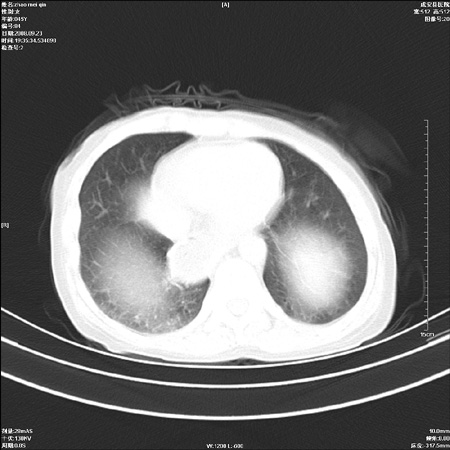

标题: CT15861:女 60 外伤后1小时 胸疼 [打印本页]

标题: CT15861:女 60 外伤后1小时 胸疼

外伤后1小时 胸疼 是外伤后引起的吗?

食道扩张明显下端逐渐变窄,倒像贲门失迟缓

食道ca术后胸腔胃,右肺挫伤?

非外伤性改变,典型的贲门失迟缓症

食道扩张明显下端逐渐变窄,大量食物存留,象贲门失迟缓症。